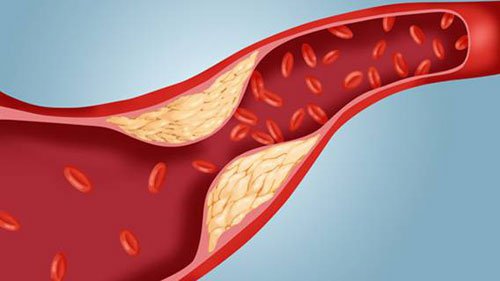

Có thể giúp ngăn ngừa bệnh tim mạch

Do tác dụng của Niacin đối với các loại cholesterol kể trên, nên chất này có thể giúp ngăn ngừa bệnh tim. Ngoài ra, chất này có thể giúp giảm căng thẳng oxy hóa và viêm, cả hai tình trạng này đều liên quan đến xơ vữa động mạch hoặc xơ cứng động mạch.

Một số nghiên cứu chỉ ra rằng nếu sử dụng liệu pháp niacin một mình hoặc kết hợp với statin có thể giúp giảm nguy cơ các vấn đề sức khỏe liên quan đến bệnh tim. Tuy nhiên, một số đánh giá gần đây đã kết luận rằng liệu pháp niacin không giúp giảm đáng kể nguy cơ đau tim, đột quỵ hoặc tử vong do bệnh tim ở những người mắc bệnh tim hoặc những người có nguy cơ cao mắc bệnh tim. Do đó, vẫn cần nhiều nghiên cứu sâu hơn để đưa ra kết luận cuối cùng về tác dụng này của Niacin.